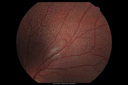

12 year old female She went last December for her regular checkup and spots were noted on the retina in the periphery. Her vision is fine and there is no family history of retinal disease. She has difficulty seeing at night and finding her way in a dark theater. VA OD: Dcc20/20-1 NccJ1+ VA OS: Dcc20/20 NccJ1+

Fundus Albipunctatusvista 962 veces12 year old female with normal vision. She has 4 siblings all of whom have either white spots or spots on IR. Genetic testing by parents was deferred.00000